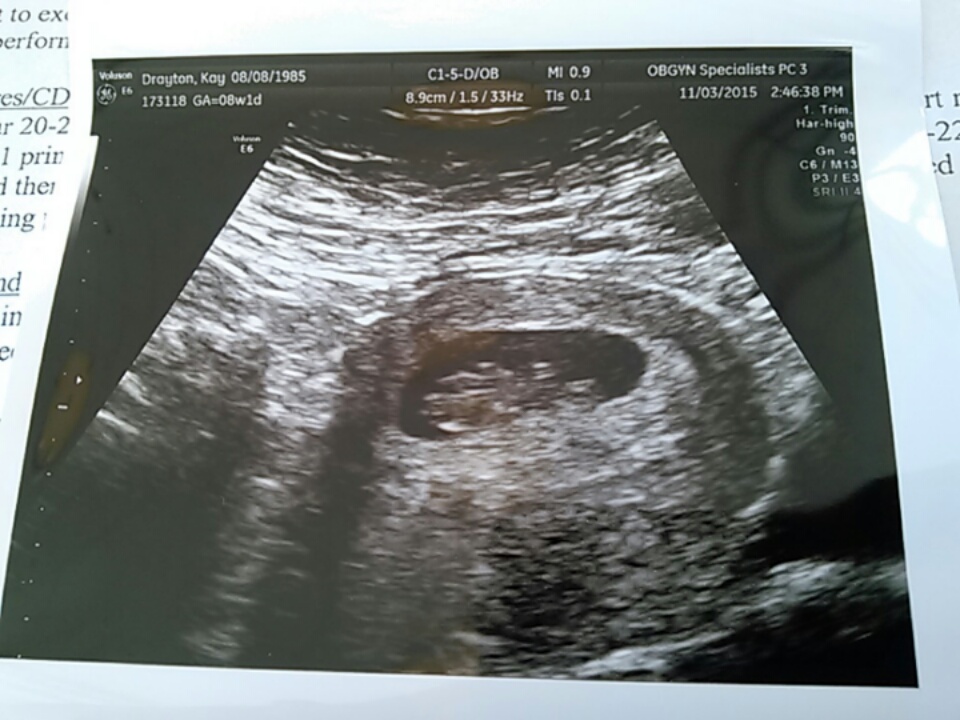

Had our first US today! Exactly 8w (LMP had me at 7w6d) and heart beat was a strong 163. All looks healthy & good. Next US is at 12w (NT scan). A bit relieved that all is well.